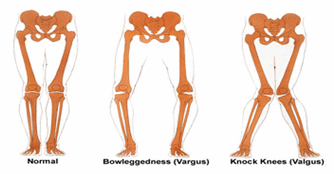

- การเปลี่ยนรูปร่างขอข้อเข่า ในรายที่เป็นมากจะมีการชำรุดของบริเวณเข่าด้านในมากกว่าด้านนอก จนทำให้กระดูกชิดชนกัน ร่วมกับกระดูกงอกที่เกิดขึ้น การเกิดกระดูกงอกที่เป็นมาก อาจจะคลำได้กดเจ็บ และก่อให้เกิดการโค้งงอขอข้อเข่า

(ภาพซ้าย: แสดงเข่าปกติ, ภาพกลาง: แสดงเข่าโค้งงอด้านนอกภาพขวา: แสดงเข่าคดชนกัน)